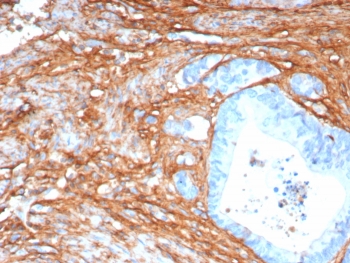

Immunohistochemistry of Periostin antibody in human colon tissue. Formalin-fixed, paraffin-embedded human colon was stained with recombinant rabbit monoclonal Periostin antibody (clone POSTN/8165R) following heat-induced epitope retrieval by boiling in pH 9 10 mM Tris with 1 mM EDTA for 20 minutes and cooling prior to testing. HRP-DAB brown chromogenic signal highlights stromal and pericryptal extracellular matrix regions surrounding colonic glands, consistent with the secreted and matrix-associated localization of Periostin, while epithelial cell nuclei remain largely negative.

In cancer research, Periostin is frequently detected within tumor-associated stroma rather than malignant epithelial cells. Elevated POSTN expression has been described in breast, lung, colorectal, pancreatic, and ovarian carcinomas, where it is often localized to cancer-associated fibroblasts and peritumoral connective tissue. This stromal distribution pattern makes Periostin antibody a valuable tool for investigating tumor microenvironment biology, epithelial-mesenchymal transition, and metastatic progression.